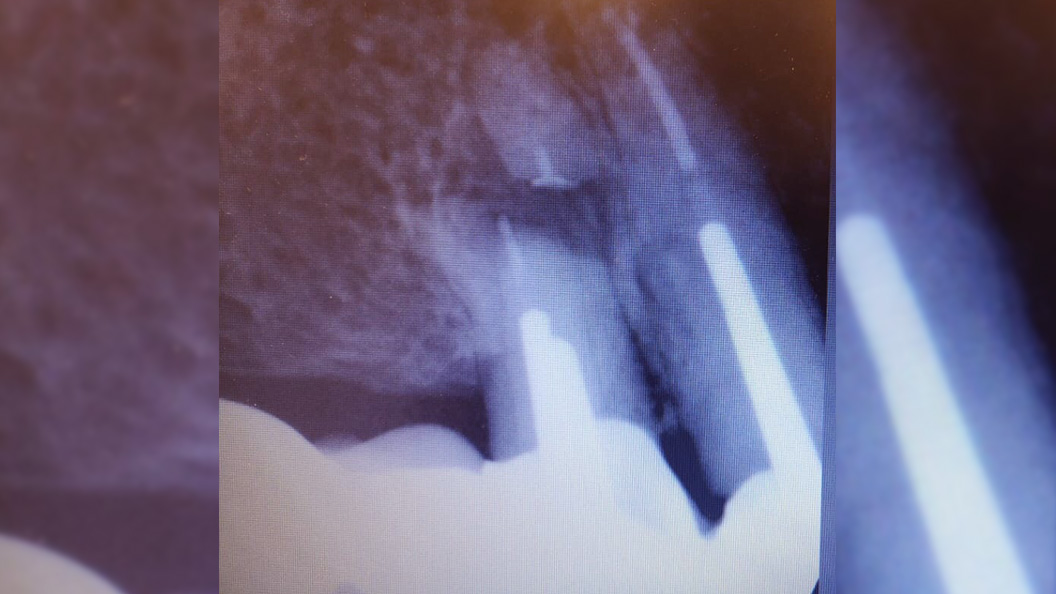

В нашу клинику обратился пациент с жалобами на резкую боль при накусывании справа вверху в области мостовидного протеза, который был установлен в другом лечебном учреждении.

После анализа сделанной рентгенограммы, врач-хирург Тарасов Денис Геннадьевич провёл резекцию верхушки корня зуба 1.4.

При неэффективности терапевтического лечения путём резекции верхушки корня одновременно с частью корня отсекается очаг воспаления в канале.